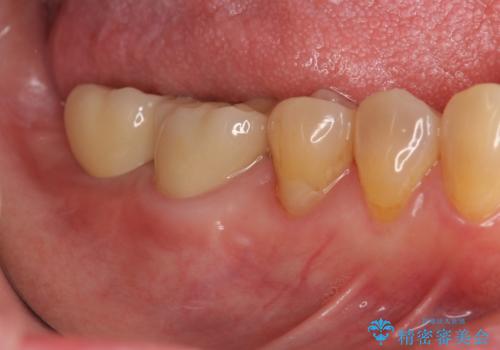

奥歯 インプラントによる機能回復

- 歯を欠損し、噛めないことの治療を希望され来院されました。

インプラントを用いて、しっかりとかめるような治療を計画します。

最後方臼歯はインプラントを用いることでしっかりと咬合機能を回復することができます。